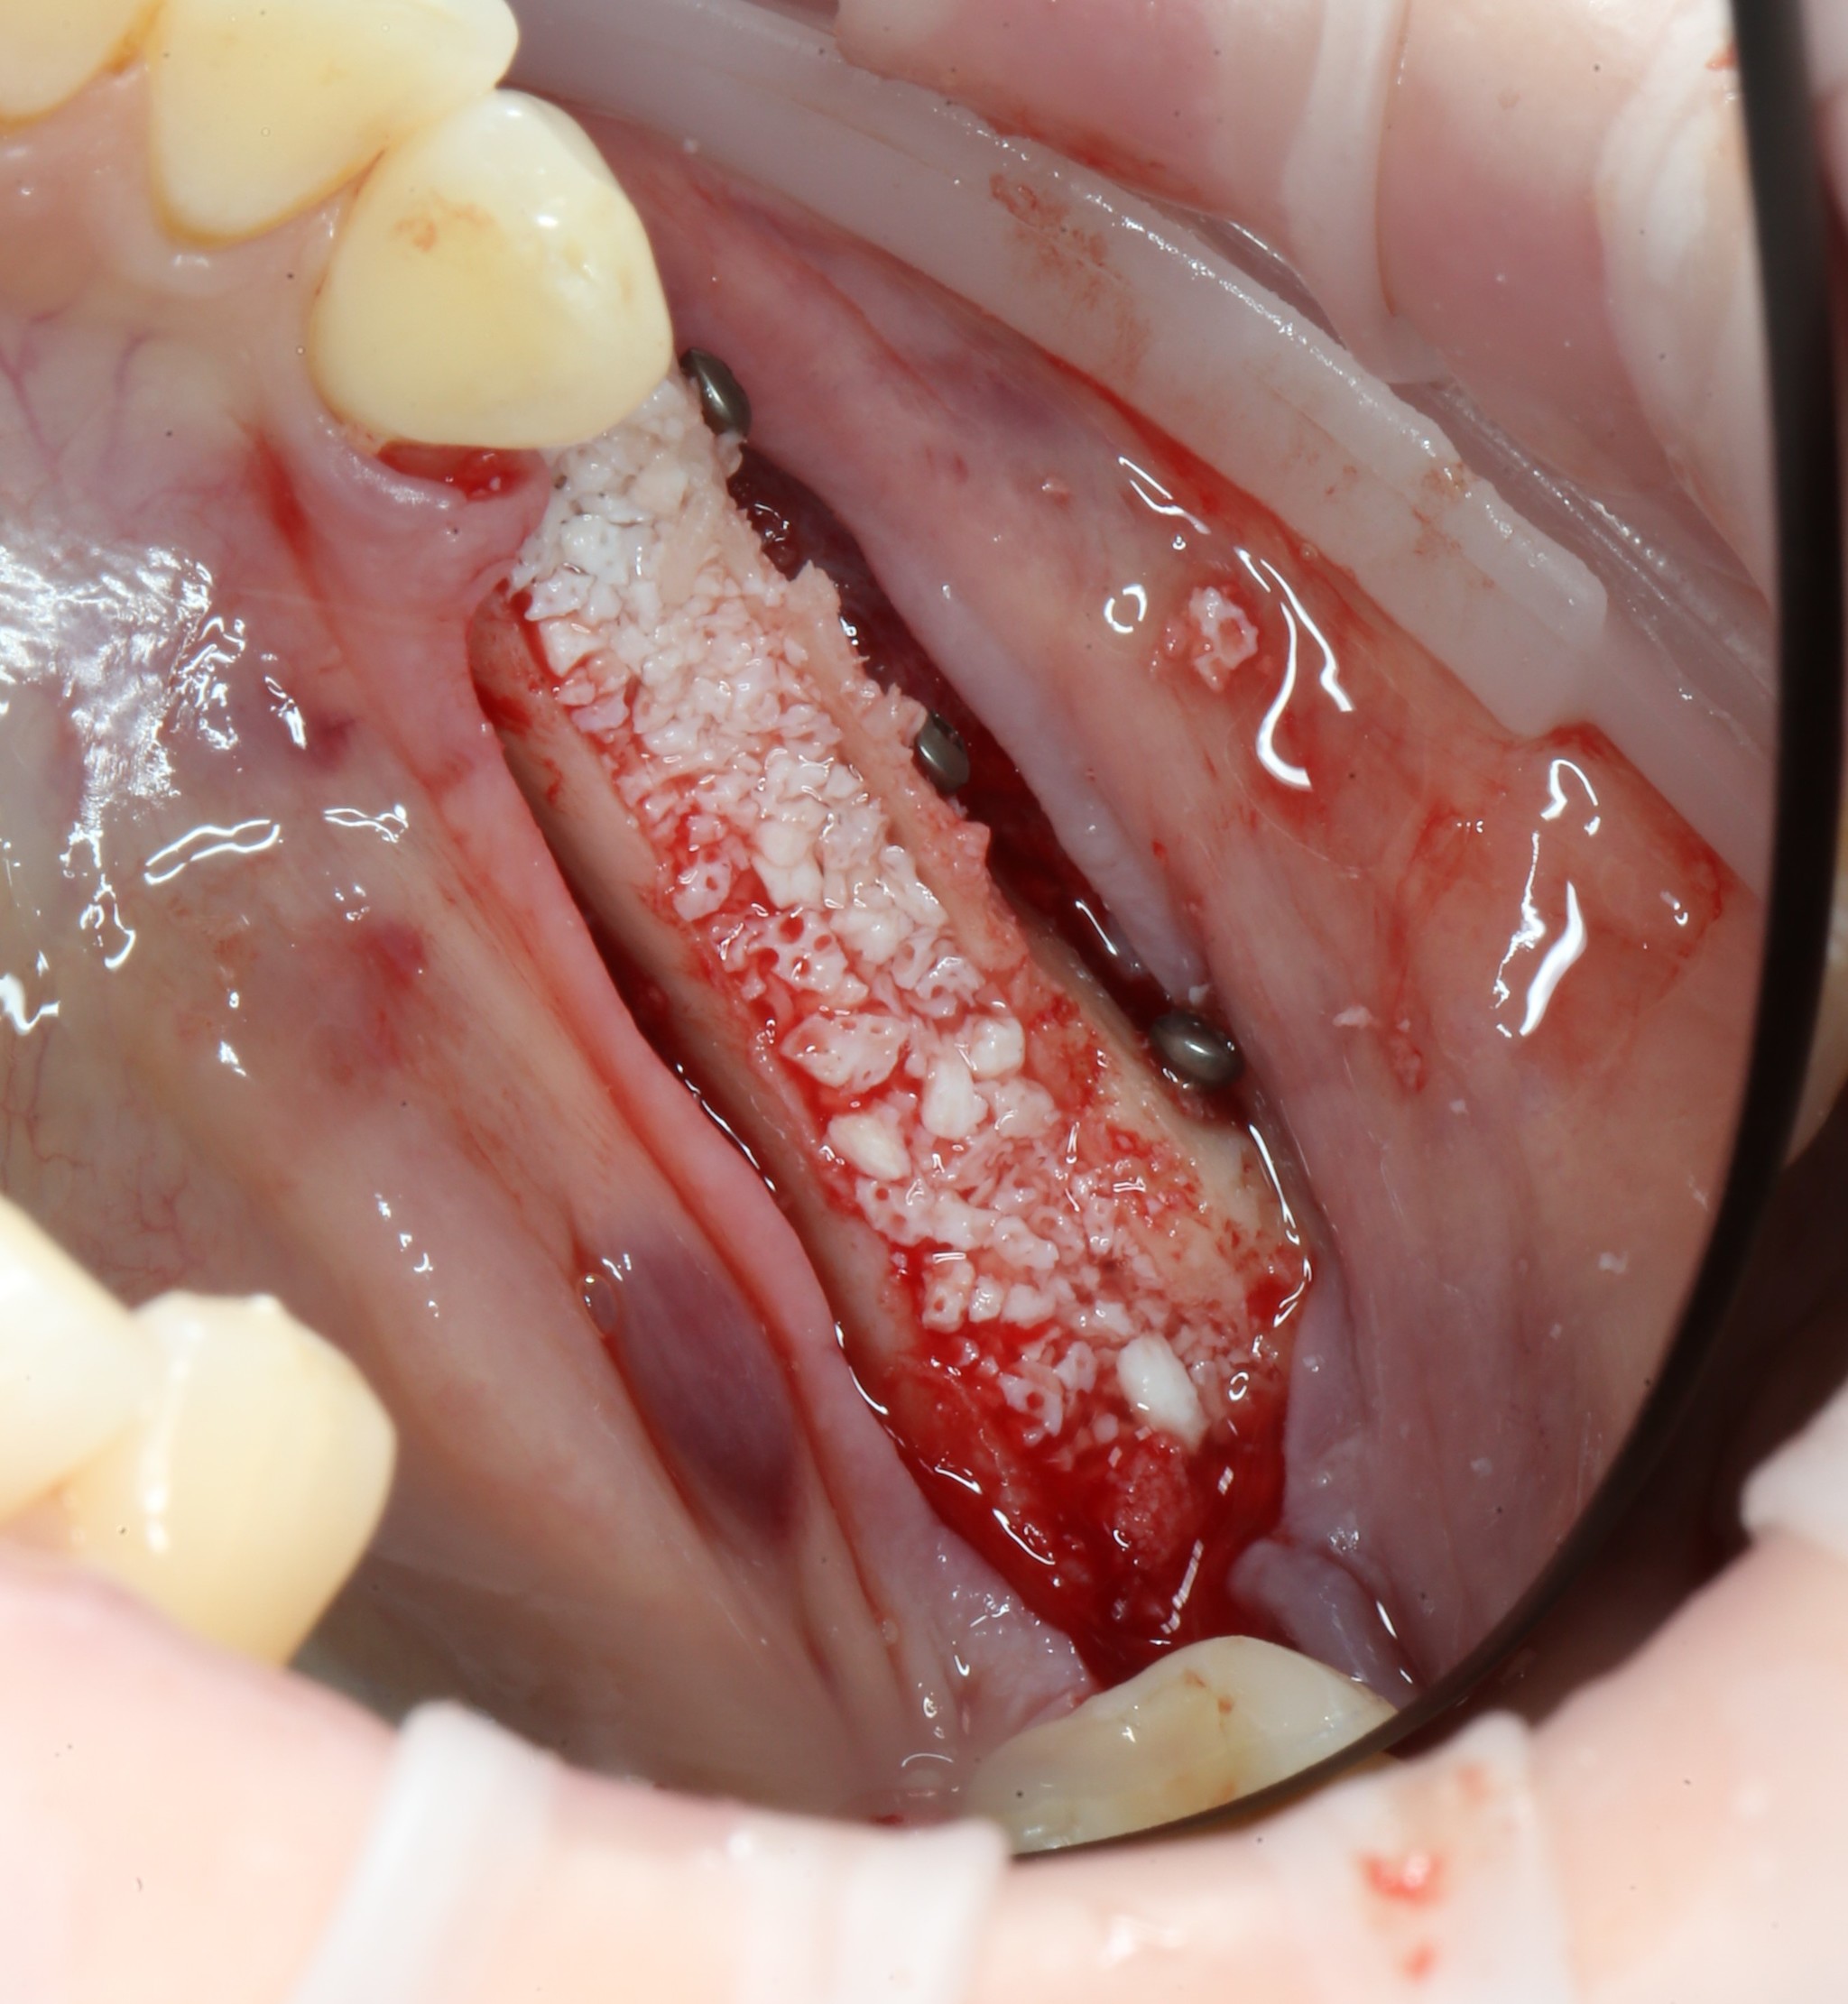

После чего распределяем костный материал:

Мягкая ткань восстанавливается намного быстрее, чем костная. Для того, чтобы десна не проросла сквозь костный материал, его необходимо укрыть специальной рассасывающейся мембраной:

Мембрана помещается между десной и костью, добавляются остатки костной стружки:

И весь этот бутерброд укрывается ею, как одеялком: